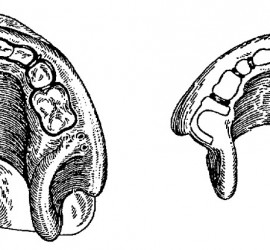

Цемент поликарбоксилатный (ТУ 64-2-275-78) выпускается Харьковским производственным объединением «Стома» (Украина). Предназначен для пломбирования молочных зубов и временных пломб, в качестве прокладок под постоянные пломбы из амальгамы, пластмассы и силикатного цемента, а также для фиксации вкладок, различных видов коронок, небольших мостовидных протезов и ортодонтических аппаратов. Поликарбоксилатный цемент выпускается в виде комплекта […]